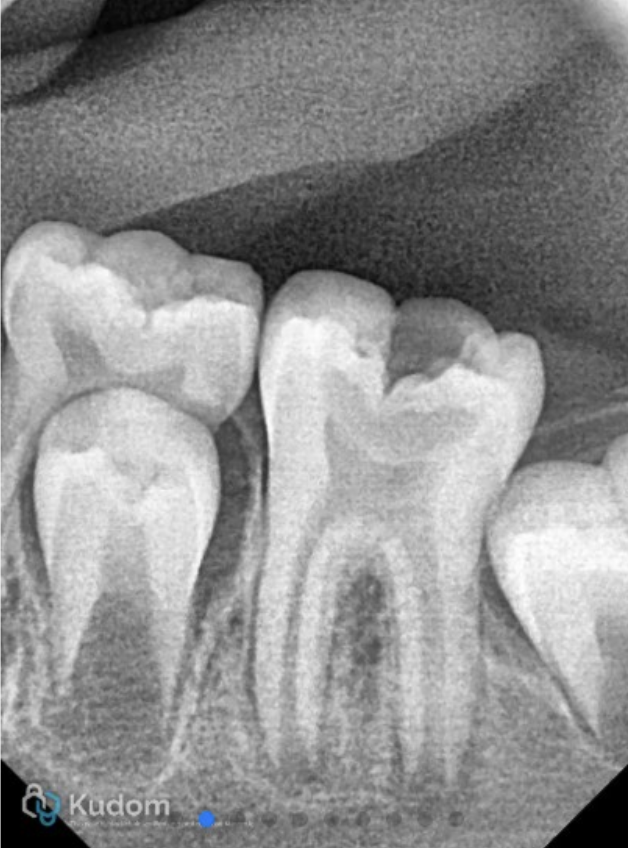

The X-ray shows the placement of calcium hydroxide medicament in the canals.